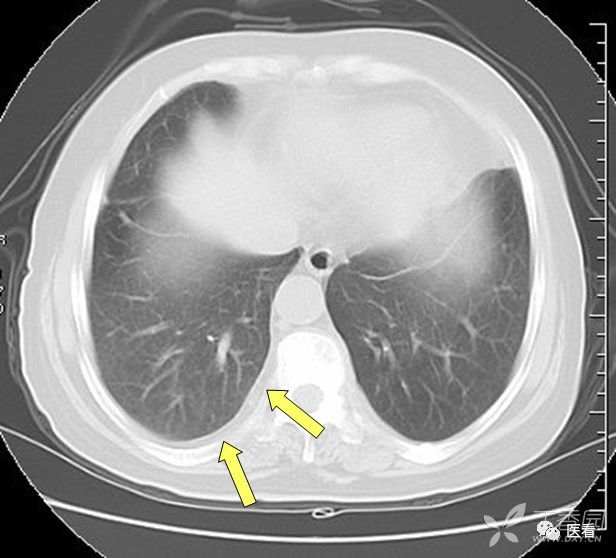

肺坠积效应

由于血液因引力作用向近地侧沉积,因此两肺下叶背侧胸膜下带血液相对较多,双肺后部肺野密度增高(箭示),称之为坠积效应。在老年人及长期卧床者尤其明显。如果不认识可能误认 为肺内炎症或肺间质纤维化。